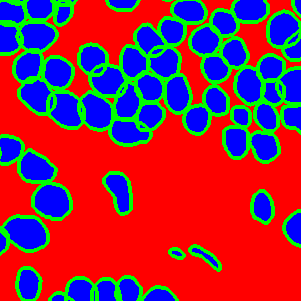

The task of nuclei segmentation can be roughly divided into two stages: the first stage is extracting the foreground(nuclei), the second stage is segmenting the connected foreground area into separated nuclei and finding out the boundary of each nucleus. Our method intends to merge these two steps by extracting the nuclei and their edges at the same time. That is the reason why it is named ”nuclei-boundary(NB) model”. As shown in Fig.3, the output of the NB model has three channels, each has the same height and width with the input image. Its values represent the probabilities of each pixel being , or class, respectively. The manual annotation for our segmentation problem is the boundary of each nucleus. A pixel belonging to the class means that it is on or inside an annotated boundary and within 2 pixel from the boundary. Pixels of the class are those that are inside annotated boundary but are not pixels. Correspondingly, the output can be regarded as an RGB image and the estimated maps of the , and are represented by red, green and blue, respectively, as shown in Fig.3. To generate the ternary mask for training, we apply a morphology operator to each nucleus to obtain the pixels, and then subtract pixels from the nucleus to get pixels.

Figure 6 shows how our method segments the nuclei step by step. The color variety is well controlled by the color normalization procedure. The prediction result shows clear nuclear areas and nucleus boundaries. In the final segmentation result and ground truth image, each nucleus is represented by a different color.

To evaluate the effectiveness of the proposed weight map and overlapped patch extraction and assembling method for extra-large image segmentation, we compared the segmentation results with and without the proposed method in Fig. 11. We can see that the raw segmentation results without using those two techniques contain obvious seams between the patches. It also demonstrates that the predictions in the border area is not accurate. As shown in Fig. 11(d), if we employ the overlapped patch extraction and assembling but without the weight map (which means all the pixels in a patch have the same weight) the segmentation result still shows noticeable seams. Fig.11(b) and Fig. 11(d) has the same stride, which is 64.